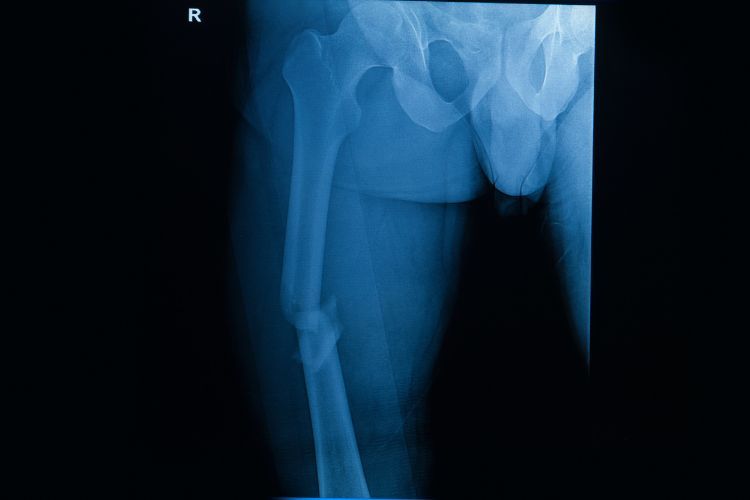

Prelom femura

Prelom femura se drugačije naziva prelom butne kosti.

Butna kost (femur) je najduža i najjača kost u telu. Pošto je butna kost toliko jaka, obično je potrebna velika sila da se slomi. Na primer, sudari motornih vozila su jedan od uzroka preloma butne kosti.

Dugačak, ravan deo butne kosti naziva se femoralna osovina. Kada dođe do preloma bilo gde duž ove kosti, to se naziva fraktura femoralne osovine. Ova vrsta slomljene noge skoro uvek zahteva operaciju da bi se izlečila.

• X-zraci. Najčešći način za procenu preloma je rendgenski snimak koji daje jasne slike kosti. Rendgenski snimci mogu pokazati da li je kost netaknuta ili slomljena. Oni takođe mogu pokazati vrstu preloma i gde se nalazi unutar butne kosti.